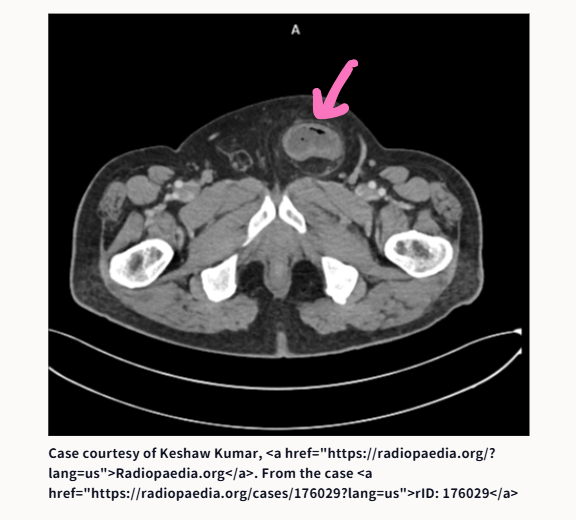

①腸閉塞です。原因は何でしょうか?

①腸閉塞の原因は、鼠径ヘルニア嵌頓でした

こあら先生が提示したCT画像は、以下のサイトからのものです。ピンクの矢印は、こあら先生が書き込んだものです。